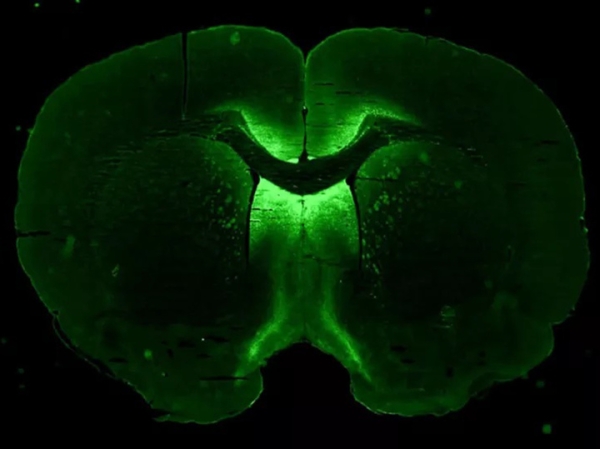

Трехмерная структура, которая была получена учеными в лаборатории из клеток мозга. Светящиеся зеленые клетки — это нейроны. Изображение предоставлено NASA Axonis Therapeutics, Inc.

Предполагается, что все три типа клеток будут «собираться» воедино, формируя небольшие сферы – «сфероиды», которые можно использовать для моделирования заболеваний головного мозга человека и для тестирования лекарств.

По словам американских ученых, космическая невесомость может стать более благоприятной средой для выращивания сфероидов, чем земное притяжение. Вырастив же мини-мозги-сфероиды, космонавты под руководством клеточных биологов протестируют на них генную терапию.